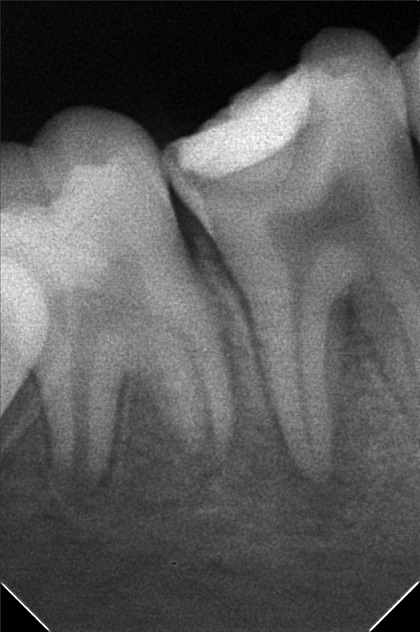

Edit Record Check our patient data records. Add patient information Patient Info Profile picture Last Name First Name Middle Name Birthdate Age Street Barangay City Country Zip Code Contact number Email Procedure 8/20/22- OP / RESTO #26 Oclusal & Disto lingual surface; #26 Occlusal & buccal pit/ EXO #65RF #46 10/19/22 - Ints of braces 50,000 less 3,999 (10,000) 11/19/22-ADJ 12/27/22-adj 01/22/23-ADJ 06/29/23-exo 14 *13 to extrude for laser/same wire 07/08/23- EXO #24 07/19/23- 14 NITI U/Lingual button #13/#13 extrude/16 Niti L 08/19/23- Extrude 13,same wire 09/16/23- same wire/ elastic Fox 13 to 43 to 44/18NiTi Lower 10/18/23- 14 NITI UPPER/ #13 BRACKET INSTALLED/ 18niti lower coil spring 44-45 ***request cbct 11/25/23- 16 NiTi U, 14 NiTi L #23 Observe all Lower towards right 12/22/23- 16 niti U/ 16 ss lower all lower move to right 01/27/24 ADJ reattachment 44 same wire adjustment all lower to the right 02/24/24 Adj-same wire chain lower reattachment #44 03/23/24 Adj reattachment #45 same wire class III elastic rabbit 04/20/24 Adj same wire chain lower 05/25/24 reattached #44 class III elastic penguin 18 SS lower w/ loop 06/20/24 #23 odontectomy near sinus 07/04/24 OP suture removal same wire class III elastic w/ loop rabbit .5 oz. 08/17/24 Reattached #44 #45 bite block 45/35 16 SS L class III elastic Q1/Q1v penguin 09/14/24 same wire 10/19/24 same wire reattached #15 11/16/24 same wire class III elastic rabbit 3oz 12/21/24 same wire chain L cross elastic Q IV to Q II 01/25/25 adj same wire reattached #35 slant elastic penguin 03/01/25 elastic slant penguin 18 SS L #35 reattached 04/09/25 elastic penguin 05/24/25 left class II rabbit right class II fox new bracket #35 reattached #11,#42 06/21/25 18 nITI U 16 SS L class III elastic chipmunk reattached #11,42 09/27/25 same wire reattached #32,15 11/15/25 Adjustment reattach #31, 32, 34 LC #34 - mesial #33 - mesial, distal #32 - mesial, distal #31 - mesial, distal #41 - mesial #42 - mesial #43 - cervical #44 - mesial 18 NITI lower Elastics- Rabbit 5oz QII-QIII class 3 12/27/25 Adjustment 02/07/26 18 SS lower Reattach #14 w/ class III Rabbit 5oz 04/15/26 Adjustment 16x16 Niti (U), chain (L) Rabbit 5oz, continue class III Replace new bracket #14, #32 05/15/26 Adjustment same wire P. chain (L) snip 34-35 rabbit 5oz for resto #44- B #41- M,D #42- D #25- O,M File abogado_kirsten.jpg File 2 abogado_kirsten_02.jpg File 3 audrey_kirsten_abogado.jpg File 4 kreistein_abogado.jpg File 5 File 6 File 7 File 8 File 9 File 10 File 11 File 12 File 13 File 14 File 15 File 16 File 17 File 18 File 19 File 20 Retain Record Retain Record Yes No Save Your Changes